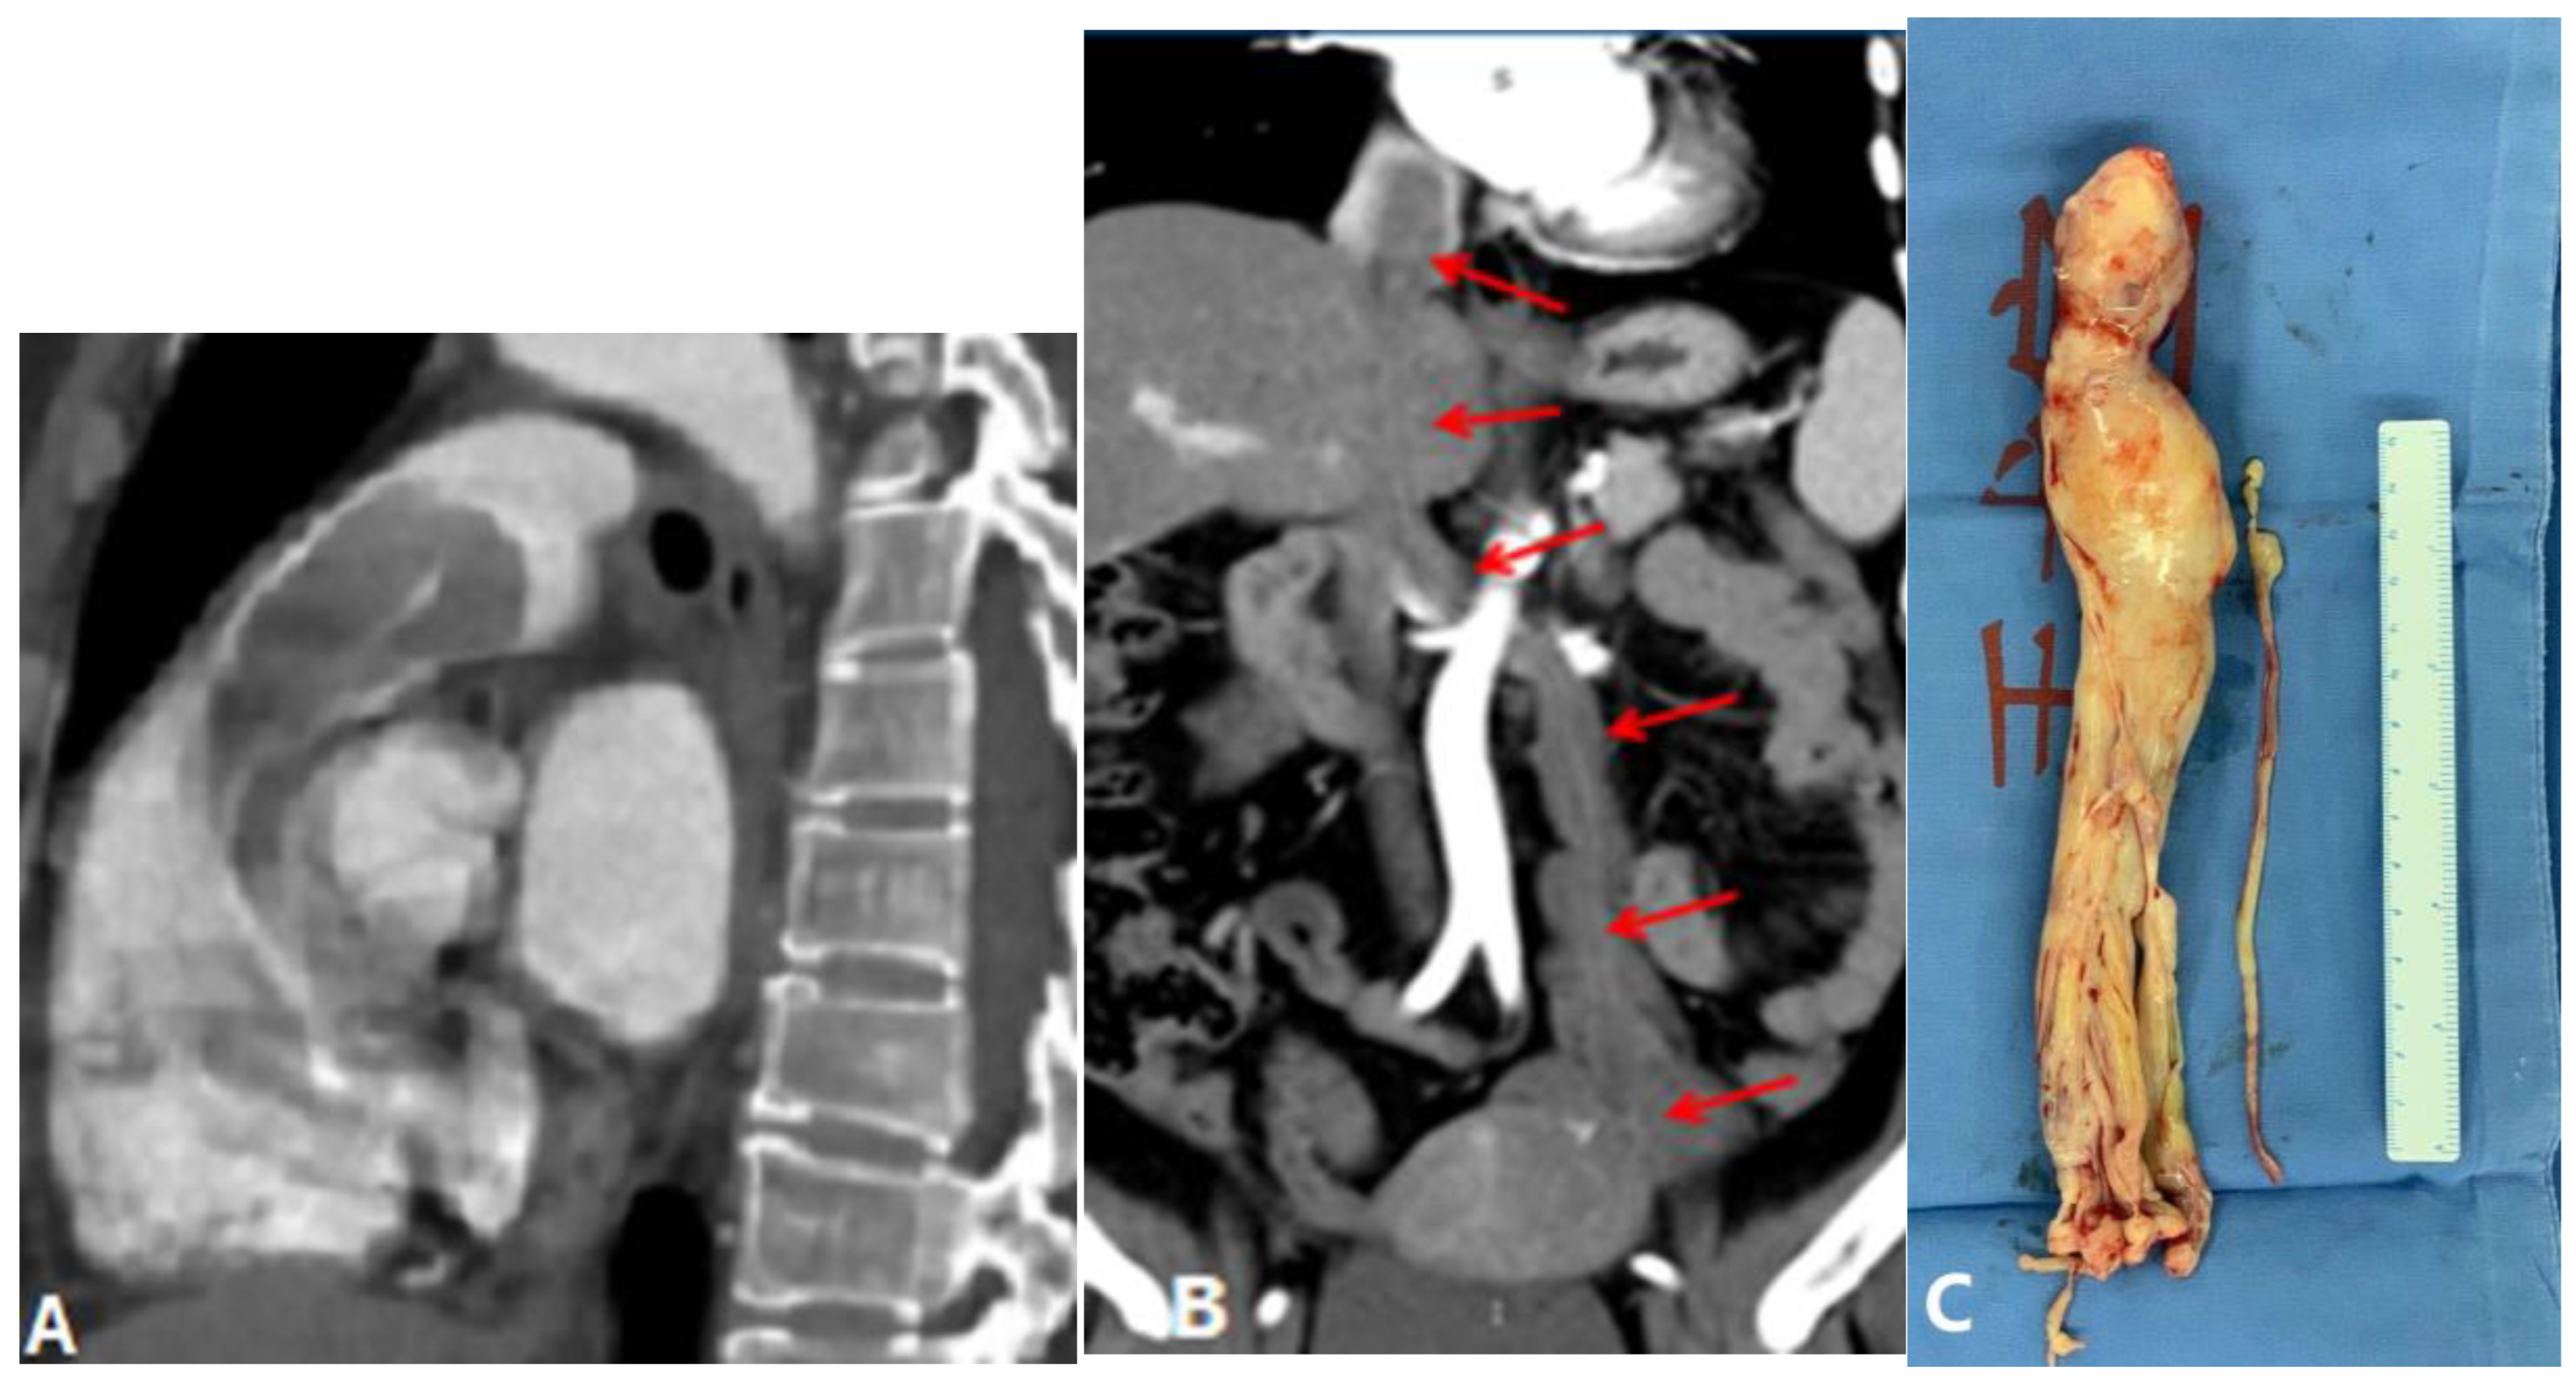

4.1.6. Pulmonary Artery Sarcoma

4.2. Vessel Wall Lesions

- Vasculitis

4.2.1. Takayasu Arteritis (TA)

4.2.2. Behçet Disease (BD)